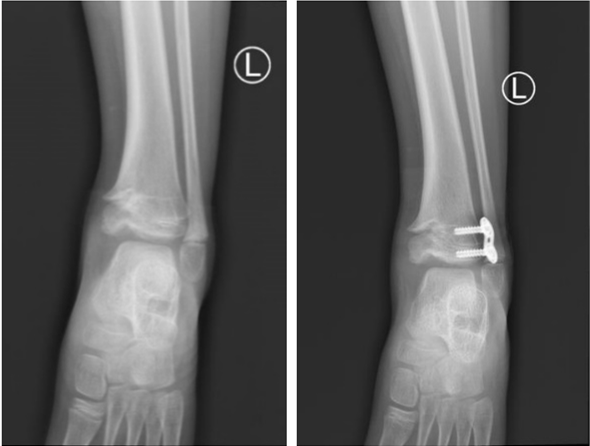

患儿为9岁男孩,因“左踝关节畸形伴行走疼痛8月余”就诊小儿骨科门诊,经详细询问病史、仔细查体、阅片后收住入院,并积极完善相关检查,组织全科医生进行病例讨论。科室主任董平详细分析患儿畸形的来源、分型及角度,刘文忠就患儿的治疗方式提出了新的见解。传统骨桥切除创伤大、对正常骺板破坏大、术中无法判断骨桥是否完整切除,部分病人存在骨桥再次形成、畸形复发的可能。基于上述原因,如何精准切除骨桥、最大限度保护正常骺板是术中关键技术。天玑骨科机器人可以解决传统手术创伤大、精准差、视野差等问题。经讨论最终决定采用机器人辅助下骨桥精准切除+外侧骨骺阻滞术。

经患儿家属同意后,在麻醉科、手术室的精心配合下,天玑机器人通过快速扫描、上传数据、重建骨骼形态,将指示器置于胫骨上获取相应部位冠状位、矢状位和水平位的图像,刘文忠团队通过屏幕精确找到骨桥的位置,精准磨除骨桥,再通过指示器的尖端探查骨桥切除的范围,相互映证。最后机器人精确设计、模拟置钉,精准完成外侧骨骺阻滞术。手术操作直观、安全、微创,最大限度保护正常骺板。术后患儿生命体征平稳,在小儿骨科病区护理团队悉心护理下,已康复出院。小儿骨科团队在精准化、智能化、微创化手术领域也迈向了新台阶。